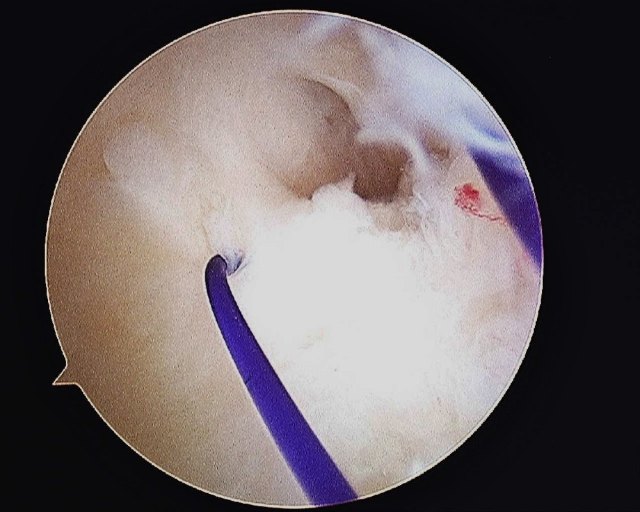

- The tear is repaired with an outside in technique with PDS 3/0 suture. The Smith & Nephew’s TFCC Mender device is used to pass the sutures through the torn TFCC. The sutures are tied outside the capsule while the ECU tendon is being protected by an assistant.

The 1st PDS suture that was passed through the TFCC is shuttled back into the joint and out of the capsule.